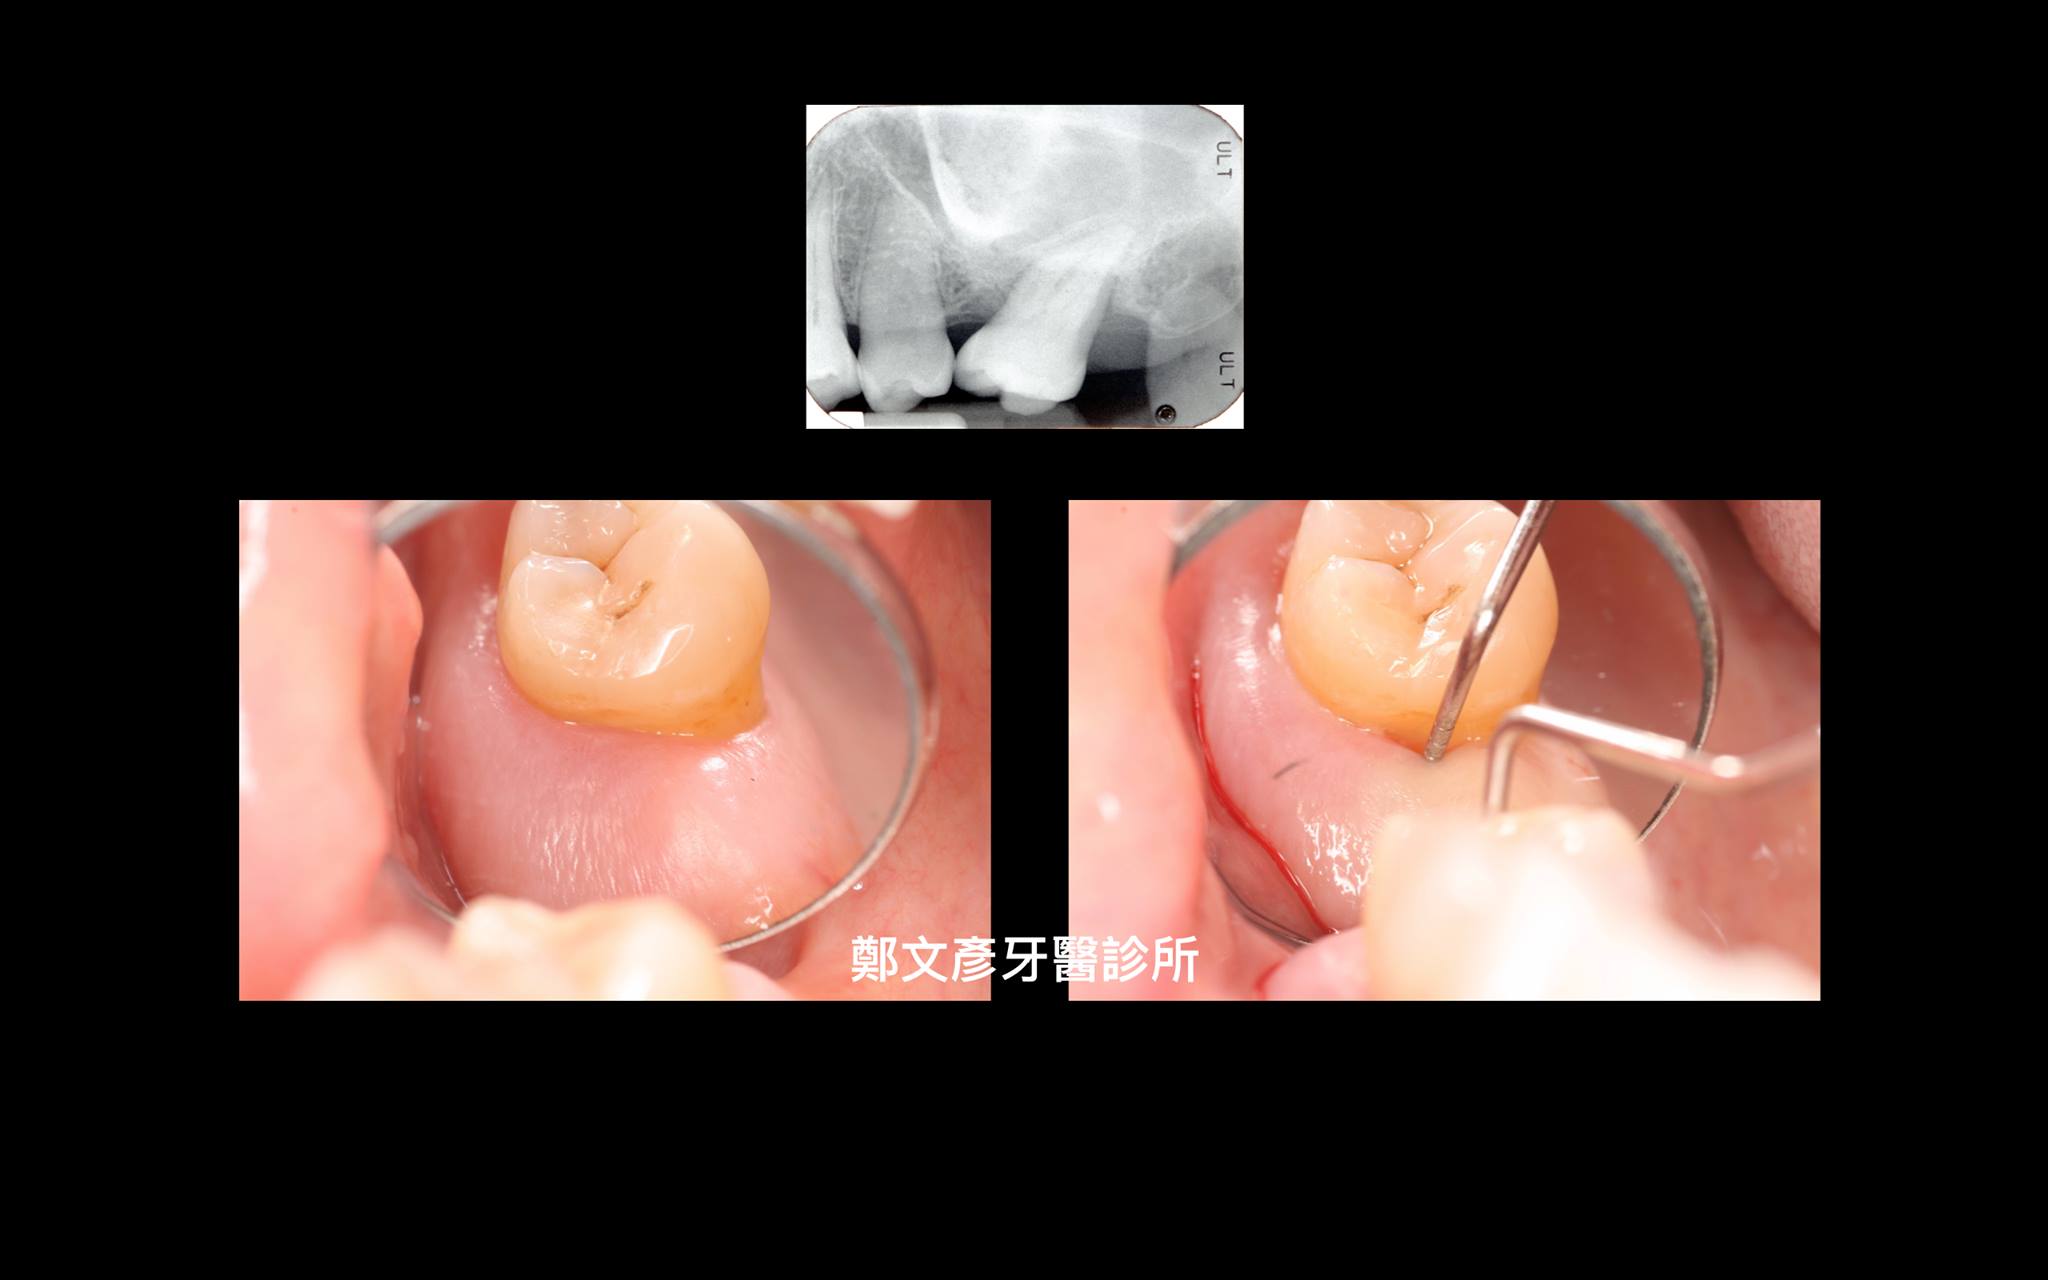

牙周再生補骨手術( GTR )4

再生補骨

牙周再生補骨手術 ( GTR )